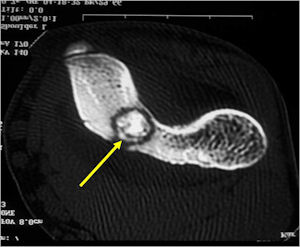

CT Scan:

- Well defined nidus with a smooth peripheral margin; +/- mineralization (CT more sensitive than XR and MRI for detecting mineralization); CT is better for detecting nidus in presence of exuberant sclerosis